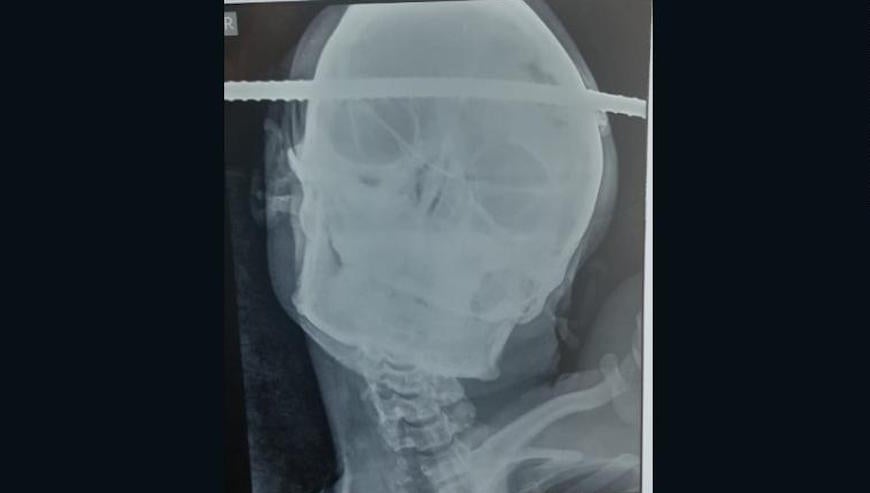

Tal y como cuentan varios medios hoy, Bahe se encontraba en medio de un trabajo de reparación en una obra de construcción cuando accidentalmente cayó en un pozo. Un accidente de una fracción de segundo que terminó con una gran barra de hierro incrustada directamente a través de su cabeza, de lado a lado.

Al parecer, después de que lo trasladaran al Hospital B.J., en la ciudad de Gondia, los médicos pudieron retirarle cuidadosamente la barra y evaluar el daño. Lo que encontraron fue ciertamente impactante. El diagnóstico encontró que la barra había ingresado en el cráneo a través de la región temporal derecha de su cerebro, y que había salido a través de la región frontal izquierda, sin embargo, de alguna forma el pedazo de metal había evitado atravesar zonas que le causaran un daño irreversible.

Finalmente, la operación fue un éxito y fue trasladado al Hospital Neuron para una cirugía adicional. Con la barra ya extraída, los signos vitales de Bahe alcanzaron la homeostasis y no sufrieron daños irrevocables en su cerebro. Dicho de otra forma, el incidente derivó en un ejemplo sorprendente de increíble suerte. Según explicó el doctor Giri: